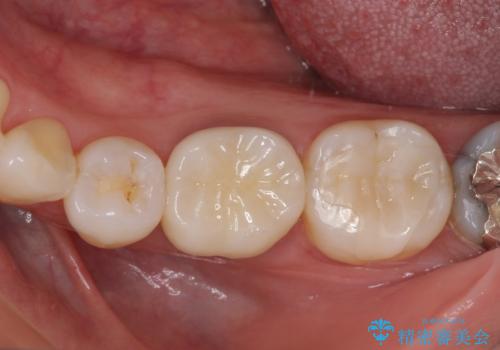

- 口を開けたときに目立ってしまう銀歯をセラミックに替えたいとのことで来院された患者様です。

上顎や親知らずにも銀歯がありましたが、今回の治療では目立つ下顎の銀歯4歯をセラミッククラウンやセラミックインレーに置き換えることにしました。

話をする度に相手の視線が銀歯に注がれている気がしているとのことでしたが、目立つ銀歯を自然な色合いに仕上げることができ、患者様には大変満足していただきました。